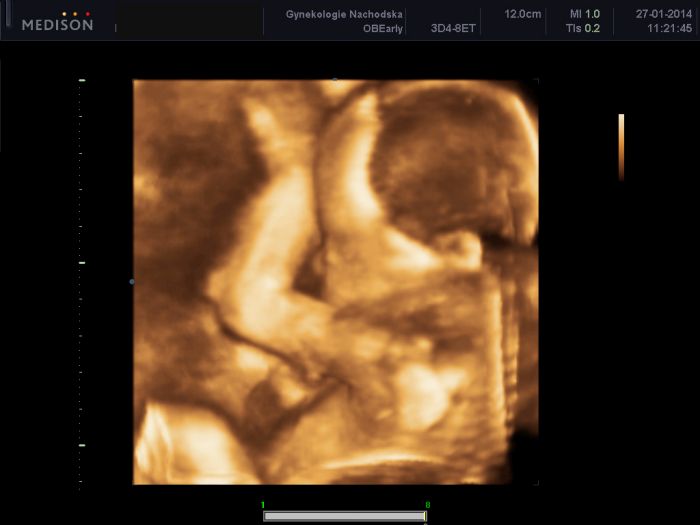

Ahoj holky moje :-) Tak prohlídka u mé Dr. proběhla v pohodě, žádný problém nevidí, a zatím stále ještě ani nevidí pindíčka, takže stále to vypadá na Emu. Ale uvidíme, jak zítra na velkém UZ. Váhový odhad je už přes 530g...takže bude asi bude větší jak Anička, toho se děsím. Jinak vše ok. A samozřejmě přikládám to naše dítko v celé své kráse :-)